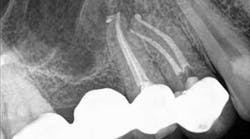

A 50-year-old male presented to my office on referral from his general dentist for evaluation of a large, periapical radiolucency relating to Nos. 4 and 5. Appropriate bitewing and peri-apical radiographs were taken (Fig. 1) for initial evaluation. After all clinical testing was performed, the recommendation was made to take a narrow-field CBCT image of teeth Nos. 4 and 5 (Figs. 2 and 3). The axial view reveals an untreated buccal canal on tooth No. 4 and potential separated instruments in both the buccal and palatal canal space of No. 5. Tooth No. 5 (Fig. 3) shows a short fill, meaning the entire canal space may not have been properly shaped and cleaned. With the three-dimensional images, we now have a better understanding of why these teeth present with post-treatment disease. This information is extremely important when discussing etiology and prognosis with our patients. It will also financially benefit the patient to maintain his existing fixed prosthesis with conservative retreatment of Nos. 4 and 5, knowing that we should have a high degree of long-term success seeing a clear etiology of the post-treatment disease.